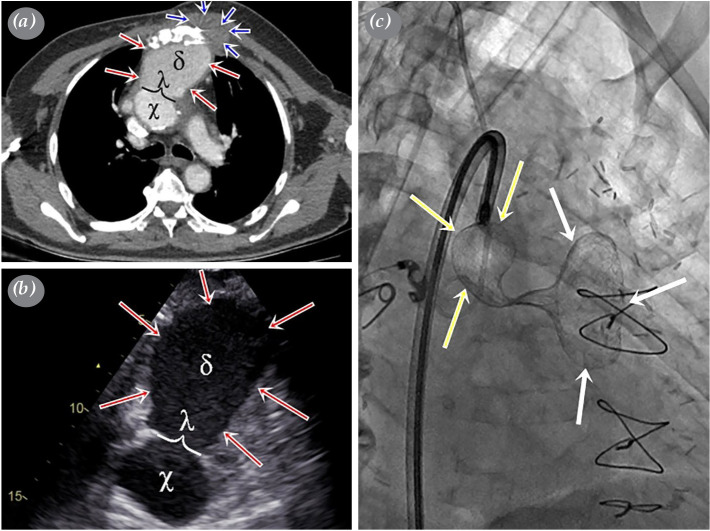

主动脉假性动脉瘤是一种罕见但严重的疾病,可导致危及生命的并发症。它通常是由以前的心脏手术、创伤或感染引起的。由于初级手术干预时血管破裂的可能性很高,在符合条件的病例中,血管内闭合可作为标准护理。在这篇文章中,我们提出了一个巨大的假性动脉瘤与宽颈,可以安全地使用房间隔封堵器关闭。

An aortic pseudoaneurysm is a rare, but serious condition which can result in life-threatening complications. It is usually caused by previous cardiac surgery, trauma, or infection. Due to the high likelihood of rupture with primary surgical intervention, endovascular closure may be performed as the standard of care in eligible cases. In this article, we present a case of a huge aortic pseudoaneurysm with a wide neck which could safely be closed using an atrial septal occluder.